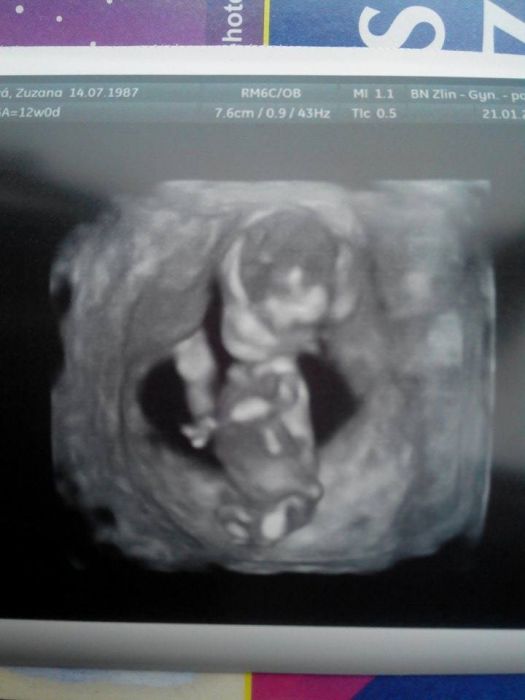

Ahojky holky, dneska mě začala strašně bolet jedna ledvina. Učitelka mě poslala okamžitě k lékaři. Udělala se prohlídka která by se dělala v pátek. Miláčkovi krásně buší srdíčko, máme 5,2 cm. :) a odpovídáme přesně 12tt+2 . :) termín mám mát teda definitivně 3.8 :) UTZ mi doktor ještě dělal spodem, aby toho bylo vidět víc. :) držím vám palečky, já teďka budu 4 týdny čekat na další prohlídku :D

abych tady taky napsala něco hezkého...tak po dnešním screeningu je vše v pořádku (měli volat do 15:00 kdyby něco bylo). Medvídek se měl k světu. Vrtěl se, slyšeli jsme srdíčko, je zase o kus větší. Tak těm co to čeká zítra a později, tak si to užijte.

Příkládám fotku :)